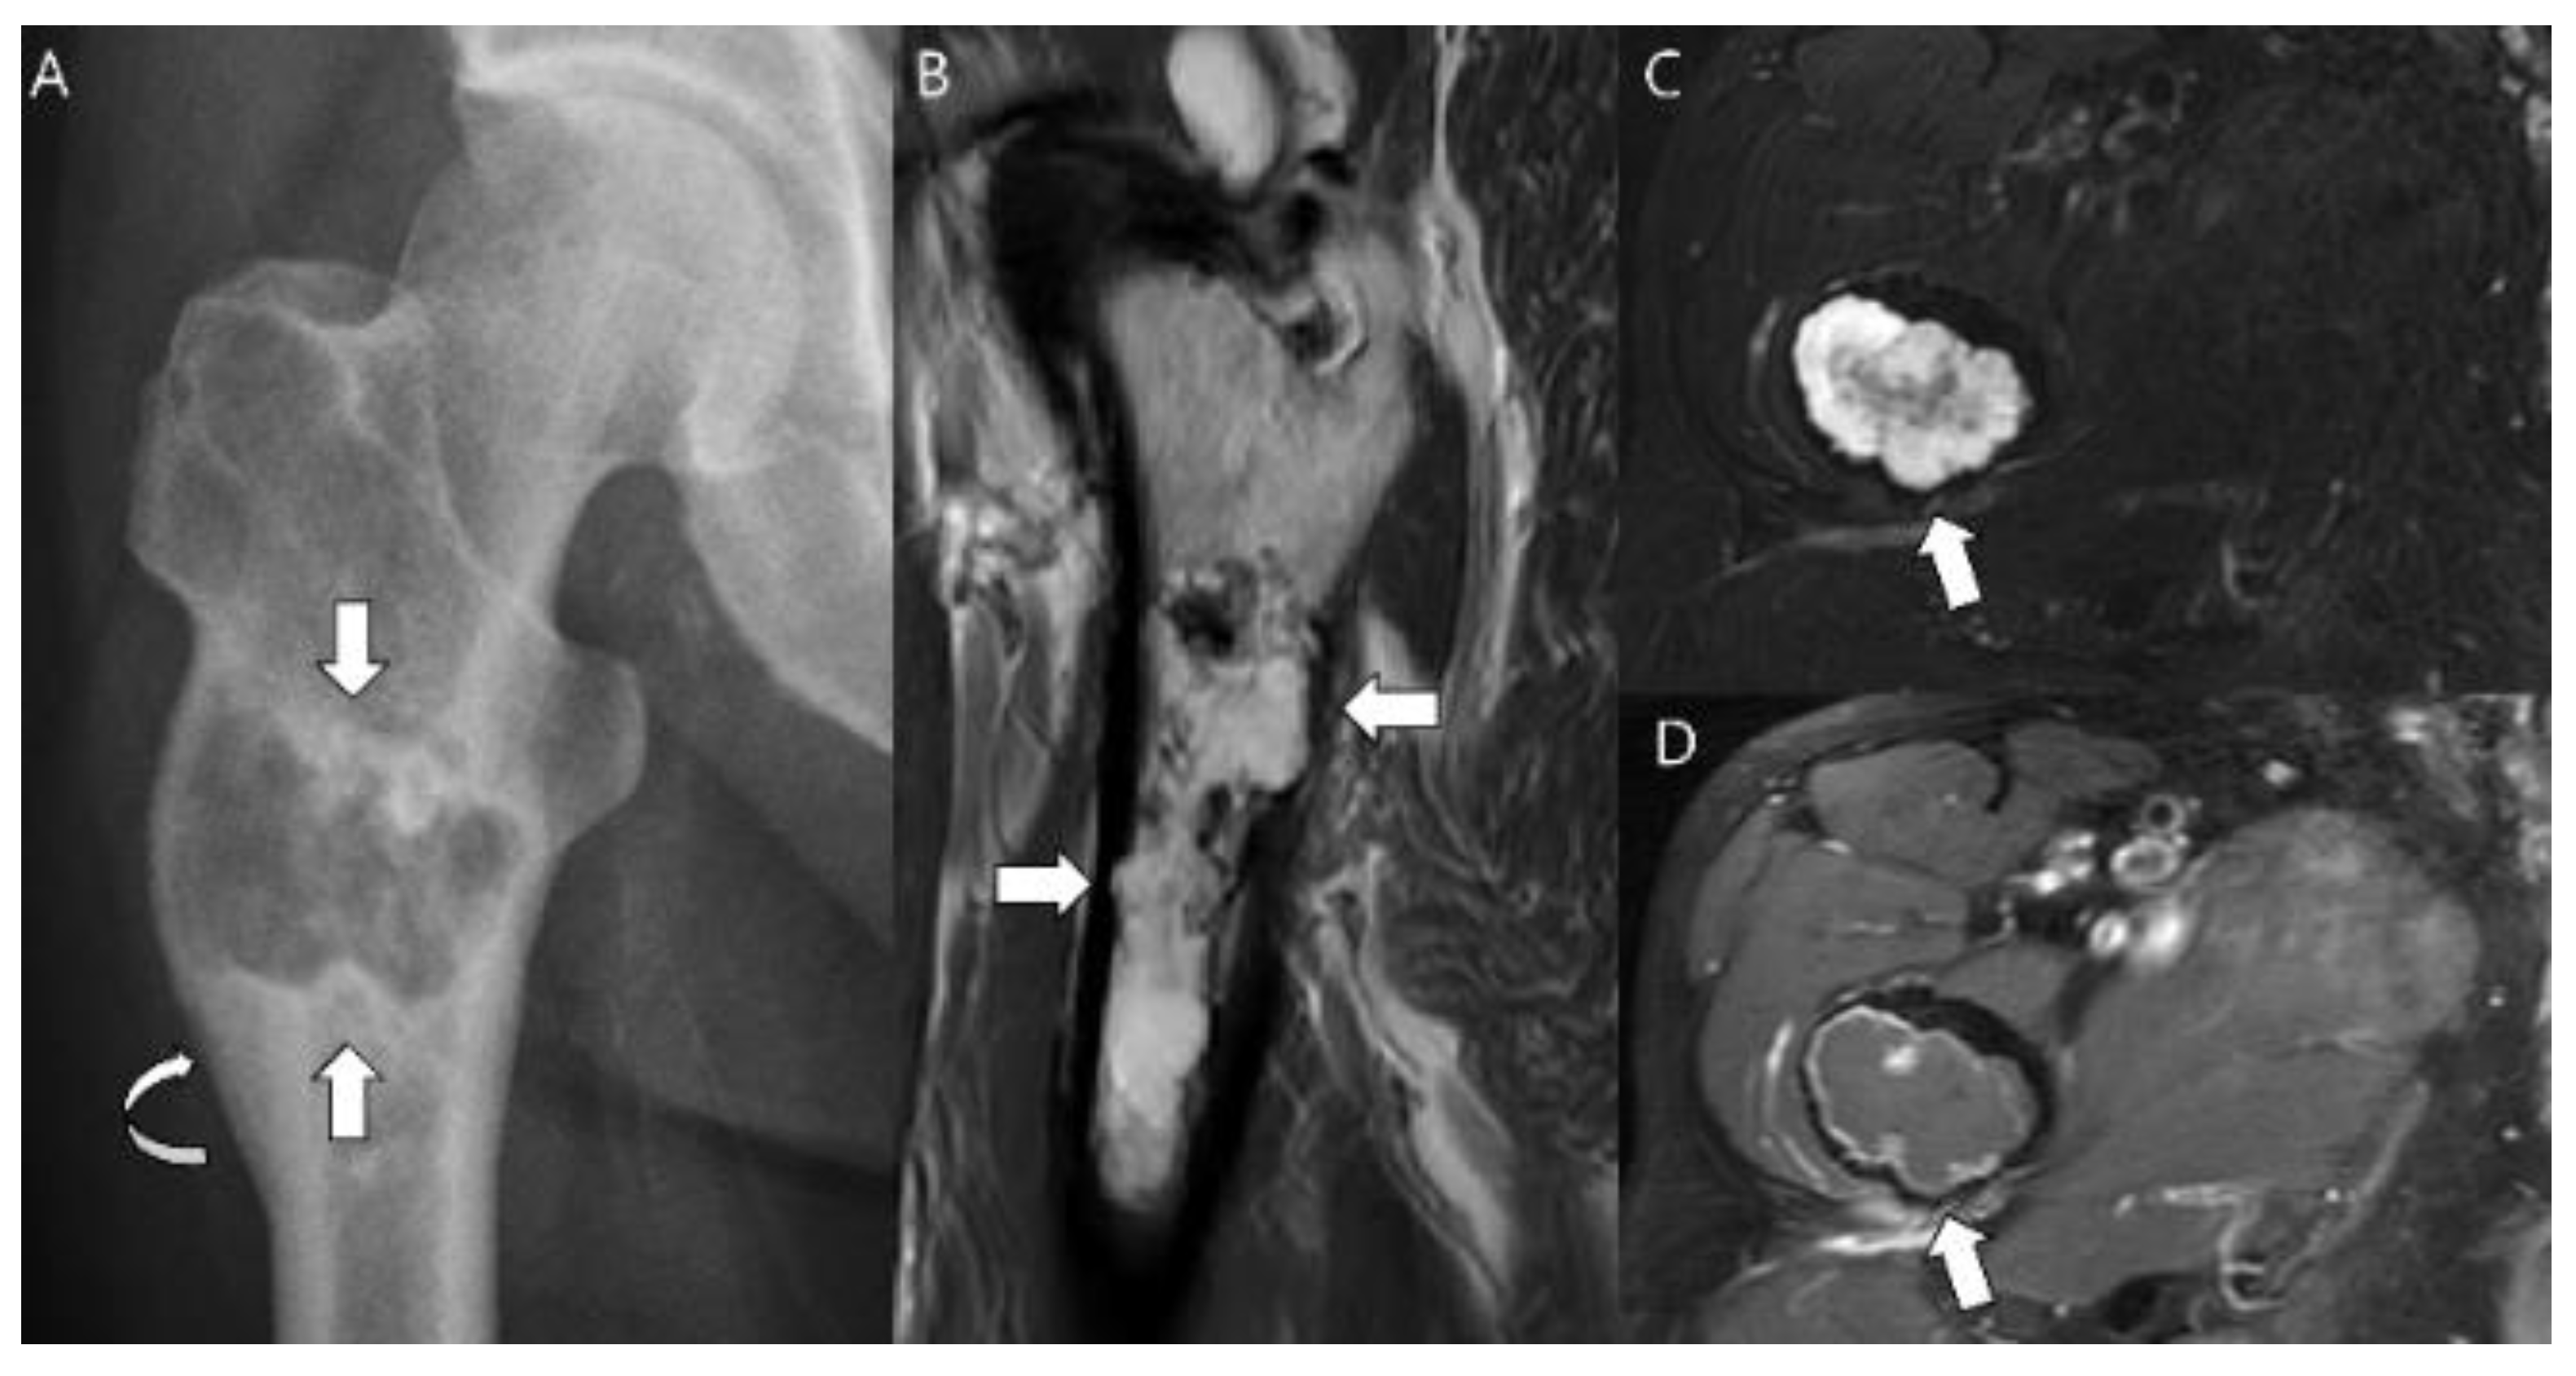

- Wuisman, P.I.J.M.; Jutte, P.C.; Ozaki, T. Secondary chondrosarcoma in osteochondromas Medullary extension in 15 of 45 cases. Acta Orthop. 1997, 68, 396–400. [Google Scholar] [CrossRef] [PubMed]

- Murphey, M.D.; Choi, J.J.; Kransdorf, M.J.; Flemming, D.J.; Gannon, F.H. Imaging of Osteochondroma: Variants and Complications with Radiologic-Pathologic Correlation. Radiographics 2000, 20, 1407–1434. [Google Scholar] [CrossRef] [PubMed]

- Lee, K.; Davies, A.; Cassar-Pullicino, V. Imaging the Complications of Osteochondromas. Clin. Radiol. 2002, 57, 18–28. [Google Scholar] [CrossRef]

- Woertler, K.; Lindner, N.; Gosheger, G.; Brinkschmidt, C.; Heindel, W. Osteochondroma: MR imaging of tumor-related complications. Eur. Radiol. 2000, 10, 832–840. [Google Scholar] [CrossRef] [PubMed]

- Norman, A.; Sissons, H.A. Radiographic hallmarks of peripheral chondrosarcoma. Radiology 1984, 151, 589–596. [Google Scholar] [CrossRef] [PubMed]

- Bernard, S.A.; Murphey, M.D.; Flemming, D.J.; Kransdorf, M.J. Improved differentiation of benign osteochondromas from secondary chondrosarcomas with standardized measurement of cartilage cap at CT and MR imaging. Radiology 2010, 255, 857–865. [Google Scholar] [CrossRef]